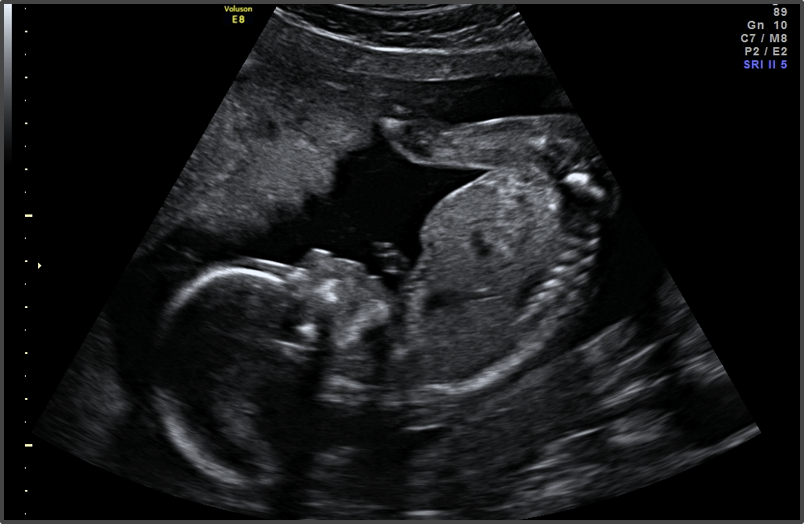

Your baby is the size of a mango.

Approx Baby Weight: 240g

Approx Baby Size: 15.3 cm

Baby Development

The baby’s nervous system is maturing.